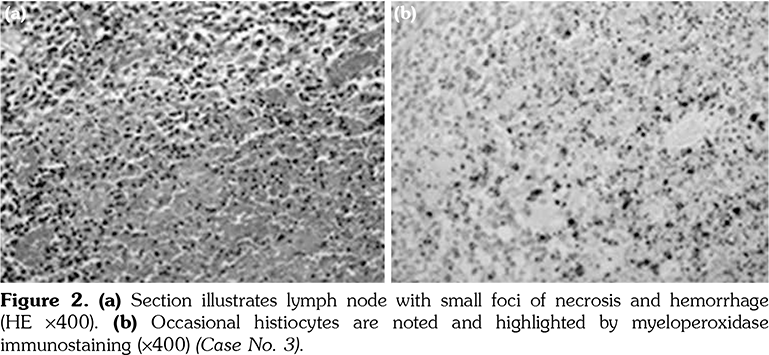

The excised cervical LNs of the 11 patients showed variable degrees of necrotizing lymphadenitis with foci of necrosis surrounded by histiocytes that are positive for CD68 and myeloperoxidase. The histopathology of the excised LN for patients numbered 2, 3, and 7 is illustrated in Figures 1, 2 and 3, respectively.

Diagnosis of KFD depends upon presence of appropriate histopathology of the lymph node (LN), which typically shows paracortical well-circumscribed necrotic lesions consisting of karyorrhexis, fibrin deposits, abundant CD68 plasmacytoid monocytes and infiltration of histiocytes in absence of plasma cells or neutrophils.[2-5]